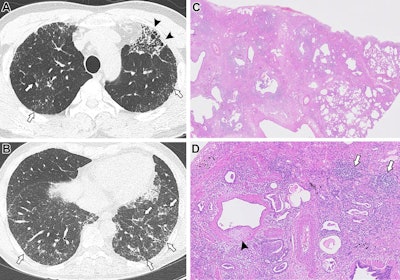

Images in a 57-year-old female with an indeterminate usual interstitial pneumonia (UIP) pattern at CT and pathologic UIP with interstitial pneumonia with autoimmune features (IPAF). (A, B) Axial noncontrast chest CT scans show a multifocal subpleural and patchy peribronchovascular distribution of ground-glass opacities, interspersed with fine reticulation and traction bronchiolectasis (arrows on A and B) that diffusely involves both lungs without a significant basal predominance. Focal areas of layered cysts with traction bronchiectasis and bronchiolectasis are noted in the left upper lobe (arrowheads on A). (C) In the pathologic specimen (original magnification, ×0.5; hematoxylin-eosin stain), the low power view shows patchy, heterogeneous involvement of end-stage fibrosis in subpleural and peripheral distribution with marked pleural and parenchymal cellular infiltration. (D) The high-power view (original magnification, ×0.5; hematoxylin-eosin stain) shows marked lymphoplasmacytic infiltration with lymphoid follicles and lymphoid aggregations (arrows) and multifocal fibroblastic foci (arrowhead). Serologic tests revealed antinuclear antibodies (titer, 1:160) with nucleolar pattern. Therefore, the patient was classified as having IPAF. The fibrosis score was 33.9% at the quantification analysis. The diffusing capacity of the lung for carbon monoxide on initial pulmonary function test was 66%. Despite use of an antifibrotic agent, follow-up CT at 1.2 years showed fibrotic progression of the interstitial lung disease (image not shown). However, the patient was alive 5.3 years after undergoing the initial CT scan. Images and caption courtesy of the RSNA.Images in a 57-year-old female with an indeterminate usual interstitial pneumonia (UIP) pattern at CT and pathologic UIP with interstitial pneumonia with autoimmune features (IPAF). (A, B) Axial noncontrast chest CT scans show a multifocal subpleural and patchy peribronchovascular distribution of ground-glass opacities, interspersed with fine reticulation and traction bronchiolectasis (arrows on A and B) that diffusely involves both lungs without a significant basal predominance. Focal areas of layered cysts with traction bronchiectasis and bronchiolectasis are noted in the left upper lobe (arrowheads on A). (C) In the pathologic specimen (original magnification, ×0.5; hematoxylin-eosin stain), the low power view shows patchy, heterogeneous involvement of end-stage fibrosis in subpleural and peripheral distribution with marked pleural and parenchymal cellular infiltration. (D) The high-power view (original magnification, ×0.5; hematoxylin-eosin stain) shows marked lymphoplasmacytic infiltration with lymphoid follicles and lymphoid aggregations (arrows) and multifocal fibroblastic foci (arrowhead). Serologic tests revealed antinuclear antibodies (titer, 1:160) with nucleolar pattern. Therefore, the patient was classified as having IPAF. The fibrosis score was 33.9% at the quantification analysis. The diffusing capacity of the lung for carbon monoxide on initial pulmonary function test was 66%. Despite use of an antifibrotic agent, follow-up CT at 1.2 years showed fibrotic progression of the interstitial lung disease (image not shown). However, the patient was alive 5.3 years after undergoing the initial CT scan. Images and caption courtesy of the RSNA.